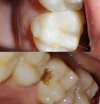

Diş Çürükleri